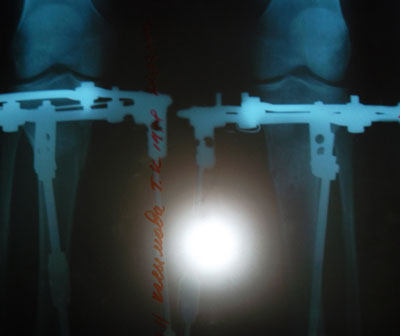

Здравствуйте! Мне сняли аппараты 29 августа, операция была 20 мая. Две недели назад приезжала на снятие, но по рентгеновским снимкам мне надо было походить несколько дней на распущенных аппаратах. Но у меня уже были взяты авиабилеты в Турцию, так как мне нужно было ходить по трапам самолёта, да вообще предстояли значительные нагрузки в дороге(это сразу после снятия аппаратов). Во избежание не желательных последствий и чтобы не потерять деньги за путёвку, Н.Н. посоветовал лететь на отдых в аппаратах и в них разрешил купаться в море, что я и с удовольствием сделала. Перелёты я перенесла легко, отдыхала и купалась в море, т.е. был полноценный отдых. Единственное, что сильно подпортила - аппараты, они заржавели.

До операции у меня были очень худые и сильно кривые ноги, настоящее колесо.

Сейчас не нарадуюсь своим ровным, новым ножкам, они мне очень нравятся! Нет тех слов, которые хочется выразить благодарность Николаю Николаевичу, это действительно специалист с большой буквы! Кстати, мы вместе оперировались и лежали в одной палате с Даной. У неё тоже получились изумительно красивые ножки. Видя её ужасный исходник до операции(а у меня было ещё и хуже), я конечно верила что будет лучше, но результат её просто поразил, это действительно волшебство.